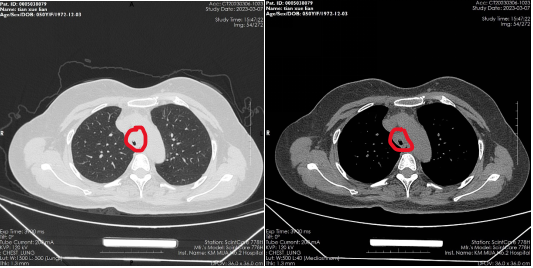

患者,女,50岁,因“外伤后呼吸困难2月”来到亚洲色吧 全科医学科治疗。患者2月前因外伤致气管撕裂,在当地医院行气管修补术,术后出现进行性加重呼吸困难。患者来到我院住院后,稍微活动就会感到气促,已不能活动,肺功能显示重度阻塞性肺通气功能障碍,胸部CT显示气管下段重度狭窄,支气管镜检查显示气管下段距隆突2cm处重度瘢痕狭窄,最窄处仅4mm,随时都会发生窒息甚至猝死,手术迫在眉睫!

气管下段狭窄治疗前